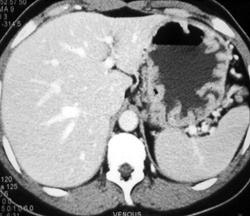

Gastritis Due to Cirrhosis and Portal Hypertension